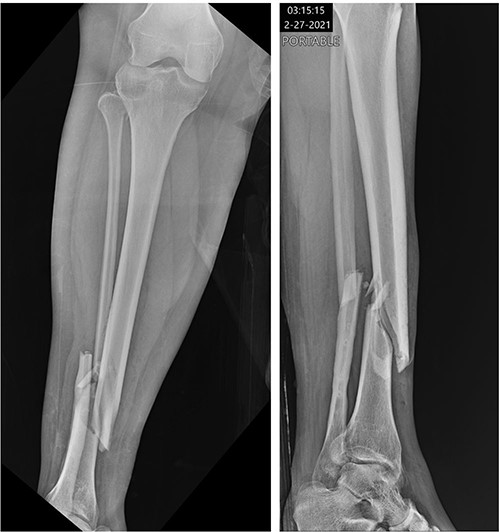

The patient was taken to the operating room on the same day for irrigation and debridement and suprapatellar nailing of the tibia. The cannula and trocar wire were driven in place, and the bone was reamed up to 11.5 mm. A 10 mm diameter Smith and Nephew nail was inserted, and two proximal and two distal interlocking screws were placed. No complications nor injury to the cartilage were noted at the time, and imaging demonstrated appropriate reduction of the fracture (Fig. 2). The patient was discharged home the next day with permission to weight bear as tolerated.

Postoperative radiographs demonstrating reduction of distal tibia/fibula fracture.